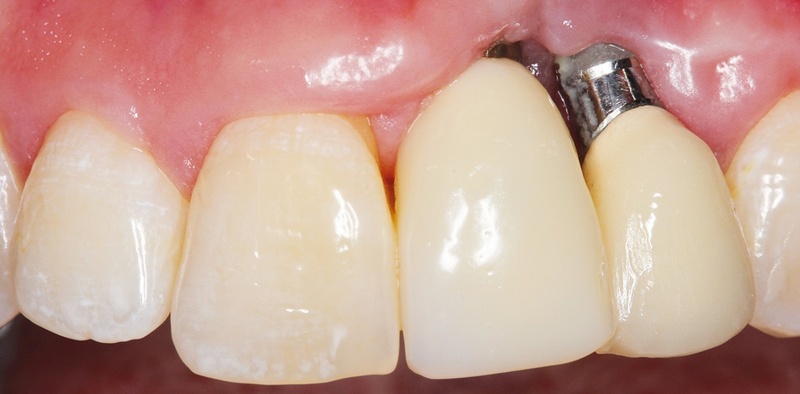

4. Tụt nướu, lộ trụ kim loại hoặc thay đổi vị trí mão sứ

Hiện tượng nướu co rút hoặc mão sứ lộ cổ kim loại có thể do viêm kéo dài khiến xương tiêu và mô nướu bị tổn thương. Nếu để lâu, implant sẽ mất hoàn toàn sự nâng đỡ.